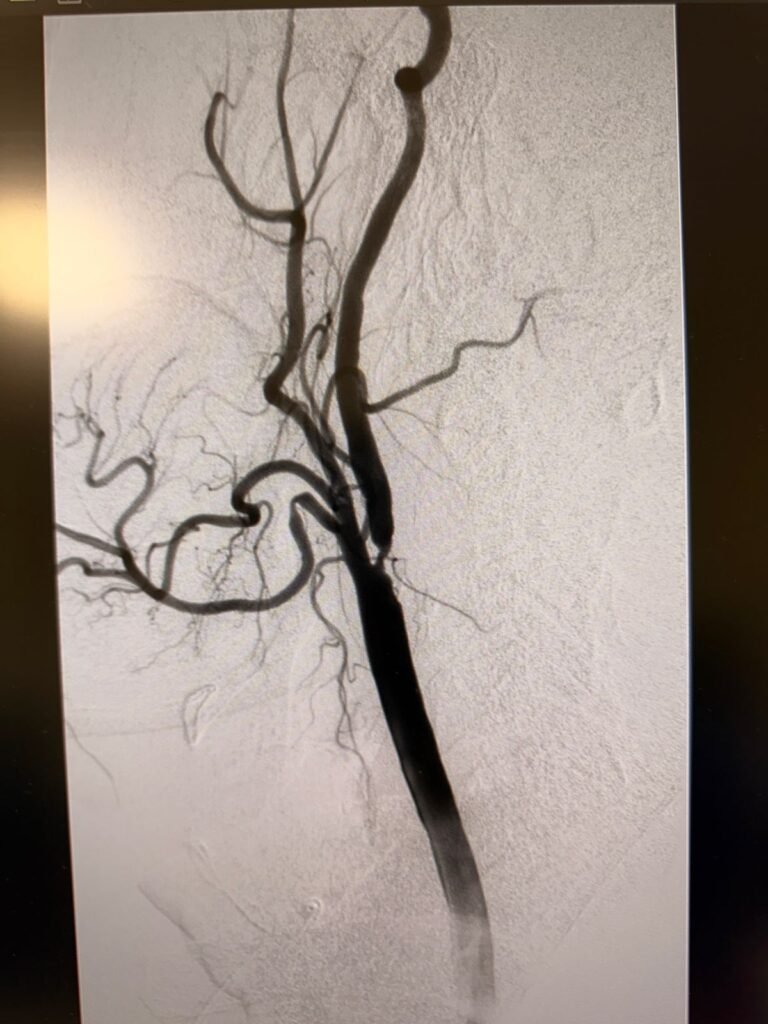

El procedimiento endovascular de alta complejidad está destinado a tratar la estenosis de las arterias carótidas y prevenir accidentes cerecerebrovasculares (ACV).

Mediante un abordaje percutáneo por arteria femoral, utilizamos filtros de protección cerebral para minimizar el riesgo de embolias durante la intervención. Posteriormente, efectuamos la dilatación con balón y la colocación de un stent de celdas cerradas, logrando una revascularización segura y eficaz, sin necesidad de cirugía a cielo abierto.